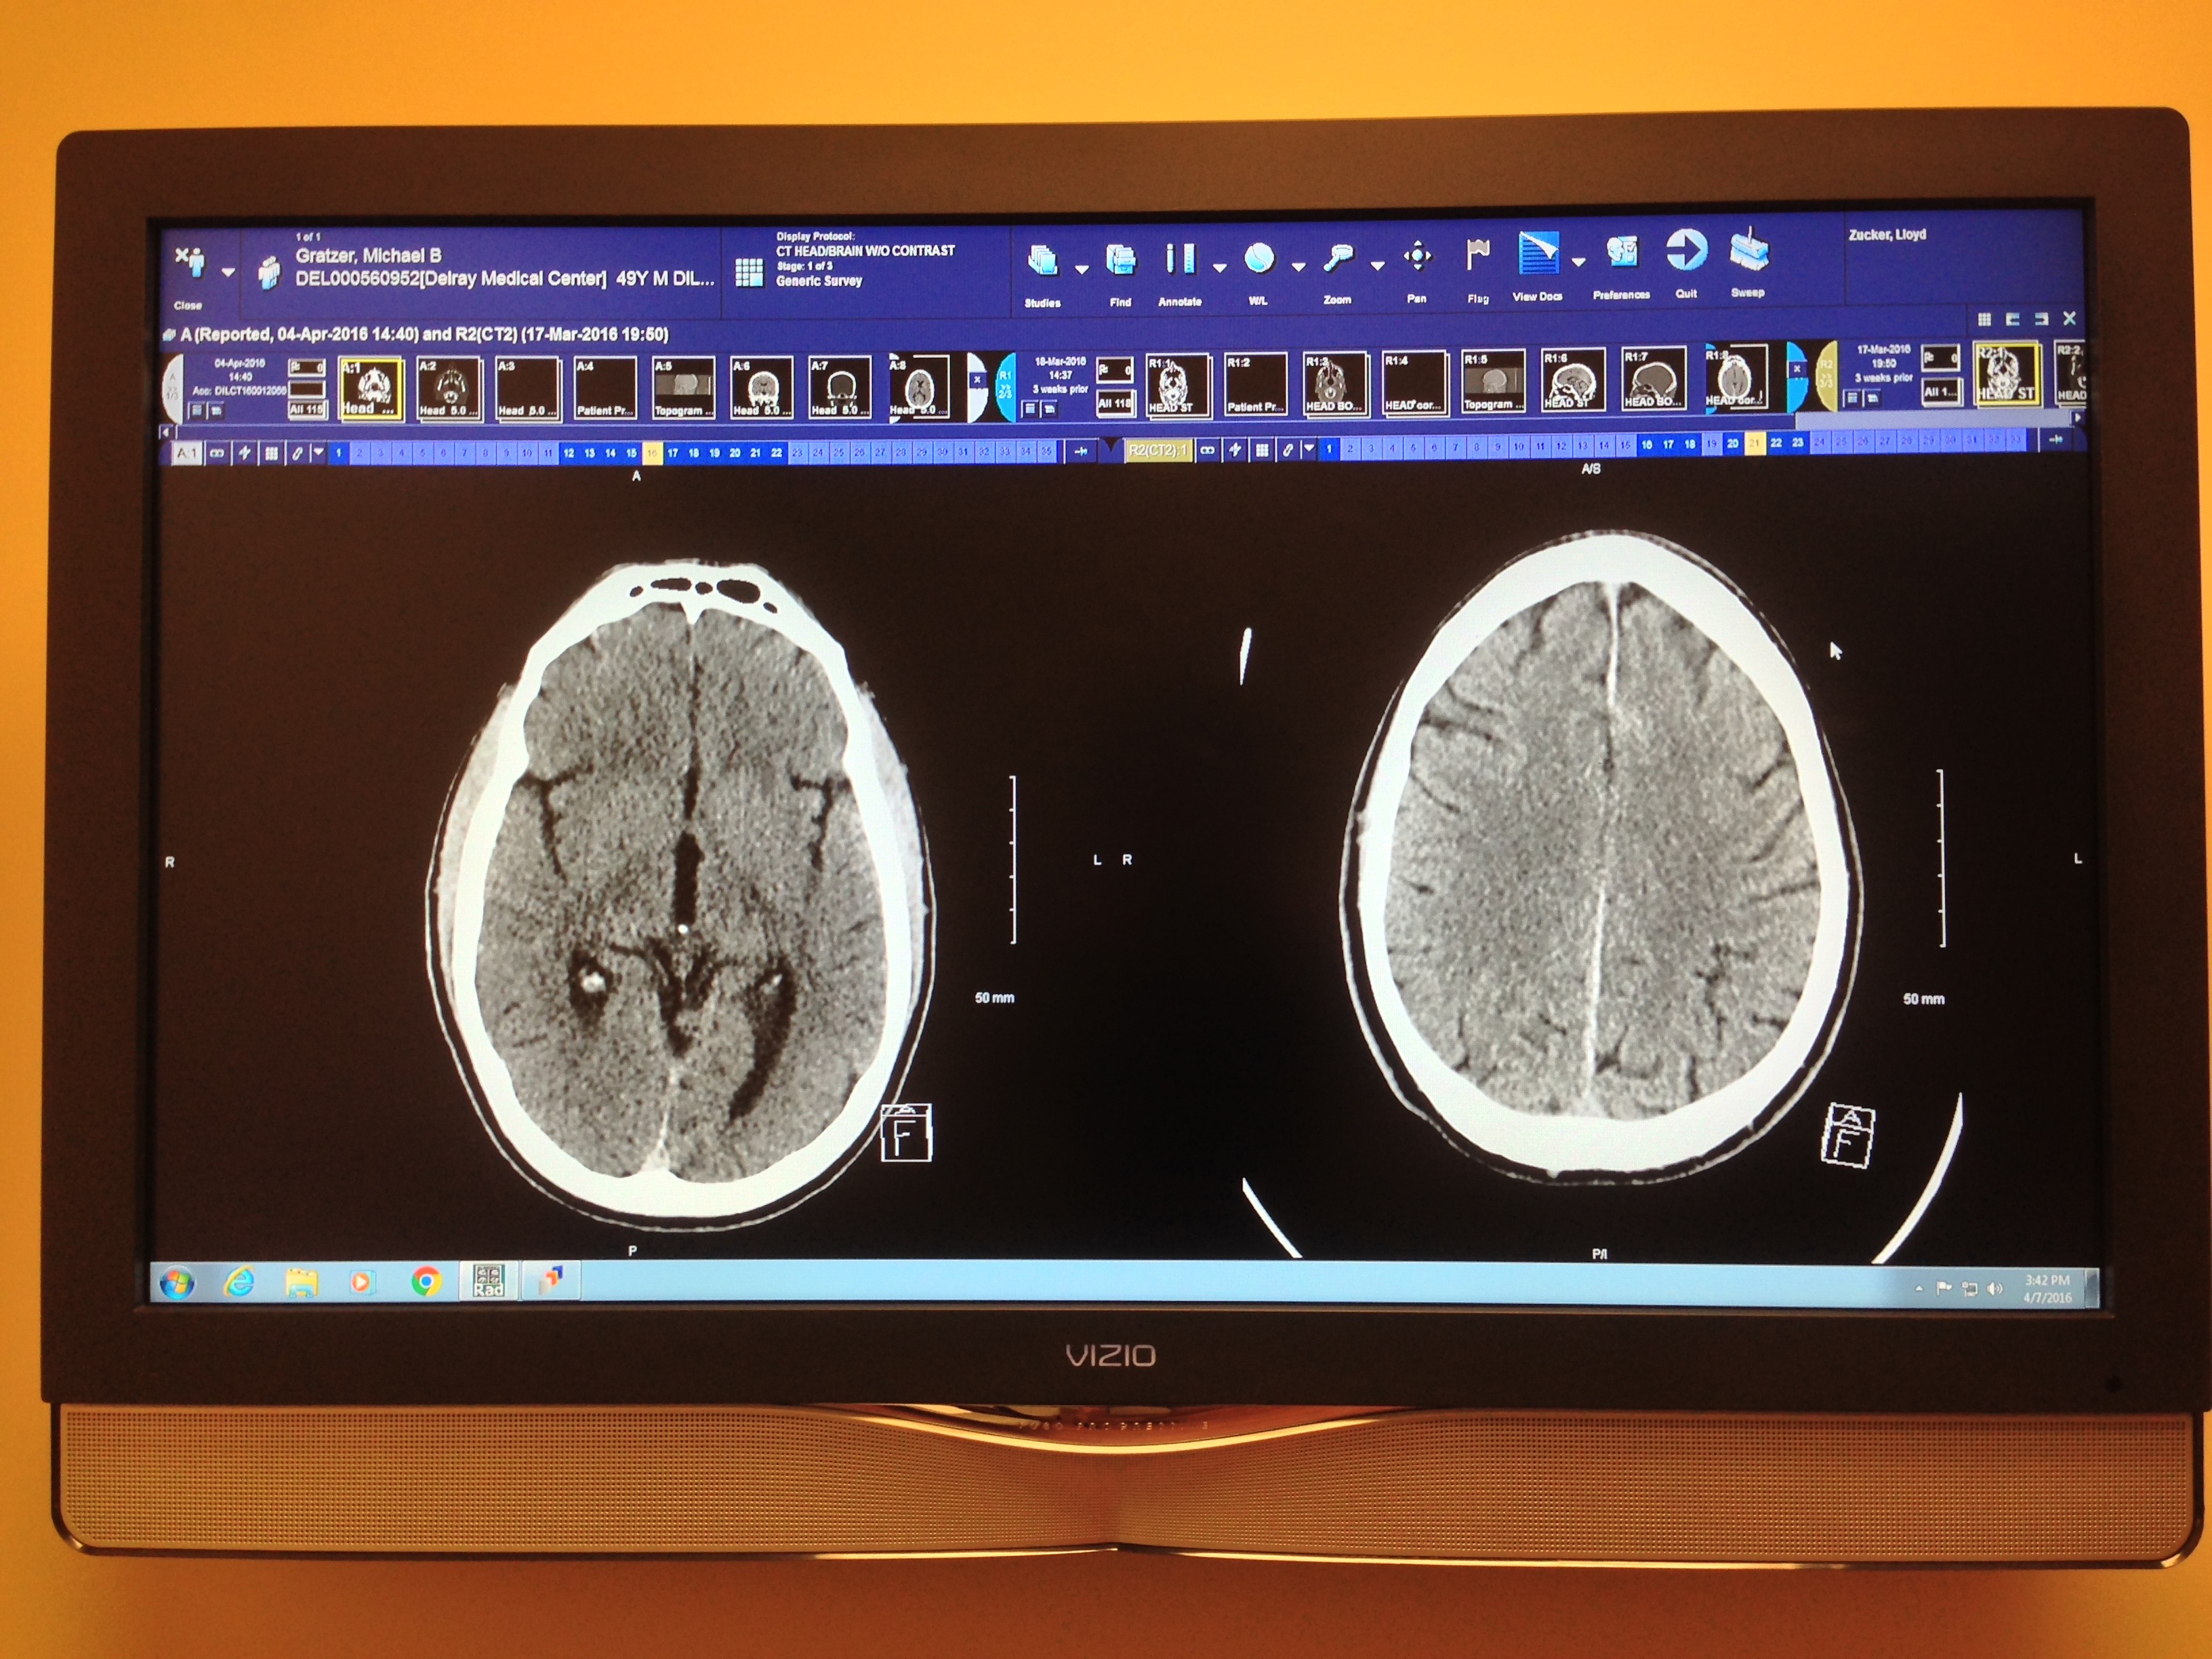

On St. Patrick’s Day 2016, my life changed forever. I was involved in a bicycle crash along the South Florida coast in Boca Raton when a rider in front of me fell, causing me to land face-first on the pavement. The impact left my face mangled and my brain suffered a subarachnoid hemorrhage. I was declared dead on the side of A1A, but miraculously, I woke up 12 days later. Since then, I have endured multiple surgeries and extensive therapy to recover, but the effects of my injury are still with me every day.